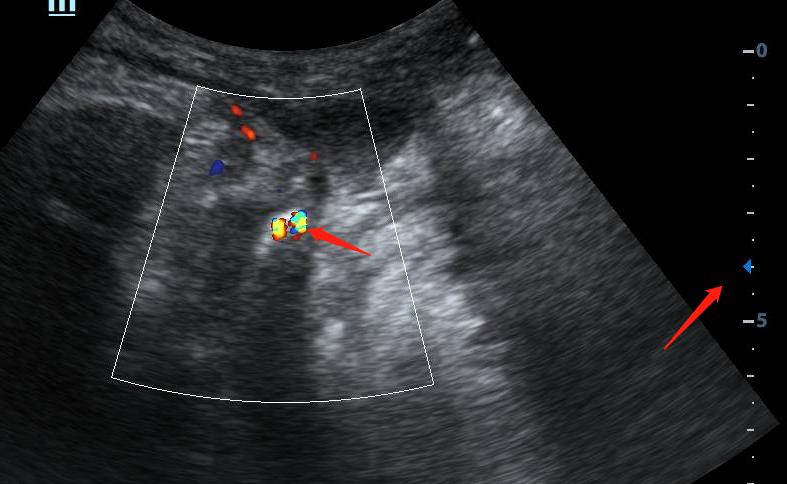

放大深度,扩大扫查后,“嗯?居然还有个大的,大小约1.0x0.6cm”远场实在看不清,换凸阵(腹部)探头。

破案了。

后尿道结石嵌顿。报告怎么写呢???交给你了,你来写。。。

鉴别诊断:前列腺钙化灶

检查方式:不必局限于探头及检查模式(当然得局限于患者同意及临床医嘱),其实在检查时我还用过腔道探头经会阴扫查,效果一般,但实际上除了以上检查方式,最有效的是经直肠超声检查。

经直肠超声可以看见尿道前列腺部及膜部的结石情况。